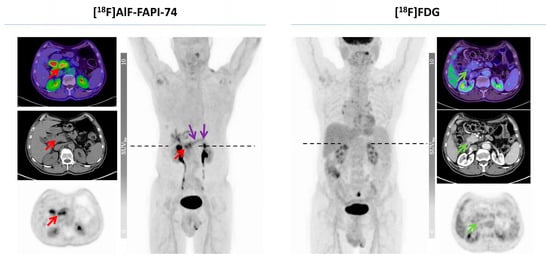

- Giesel, F.L.; Adeberg, S.; Syed, M.; Lindner, T.; Jiménez-Franco, L.D.; Mavriopoulou, E.; Staudinger, F.; Tonndorf-Martini, E.; Regnery, S.; Rieken, S.; et al. FAPI-74 PET/CT Using Either 18F-AlF or Cold-Kit 68Ga Labeling: Biodistribution, Radiation Dosimetry, and Tumor Delineation in Lung Cancer Patients. J. Nucl. Med. 2021, 62, 201–207. [Google Scholar] [CrossRef]

- Novruzov, E.; Giesel, F.L.; Mori, Y.; Choyke, P.L.; Dabir, M.; Mamlins, E.; Schmitt, D.; Antke, C.; Pinto, C.; Soza-Ried, C.; et al. Head-to-Head Intra-Individual Comparison of Biodistribution and Tumor Uptake of [18F]FAPI-74 with [18F]FDG in Patients with PDAC: A Prospective Exploratory Study. Cancers 2023, 15, 2798. [Google Scholar] [CrossRef] [PubMed]